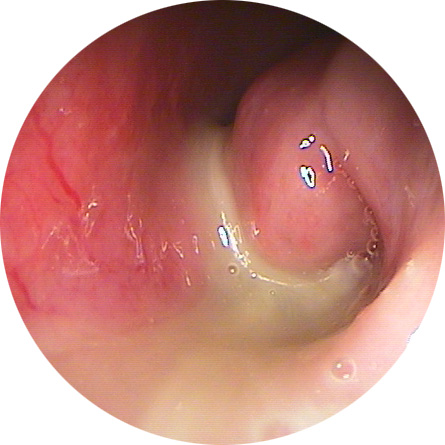

코막힘의 원인으로는 알레르기성 비염, 코 내부의 변형, 감기, 건조한 공기 등이 있습니다. 알레르기성 비염은 미세먼지, 연기, 꽃가루 등이 알레르기를 유발하여 비강의 염증을 악화시키게 됩니다. 또한, 코 내부의 변형은 부비동염(축농증), 비중격만곡증, 하비갑개비후 등이 있으며, 이는 약물로는 근본적인 치료가 어려워 수술을 받아야 하는 경우가 대부분입니다. 그 외에 건조한 공기나 감기 등도 코막힘의 주요 원인이 됩니다.

코막힘이 장기간 지속되거나 심각한 경우에는 전문의의 상담이 필요합니다. 만성 비염, 부비동염 등은 약물 치료나 수술적 치료가 필요할 수 있으므로, 조기 상담을 통해 코막힘 원인을 정확히 파악하고 치료받는 것이 중요합니다. 이 포스팅이 코막힘으로 고생하시는 분들에게 도움이 되었기를 바랍니다.